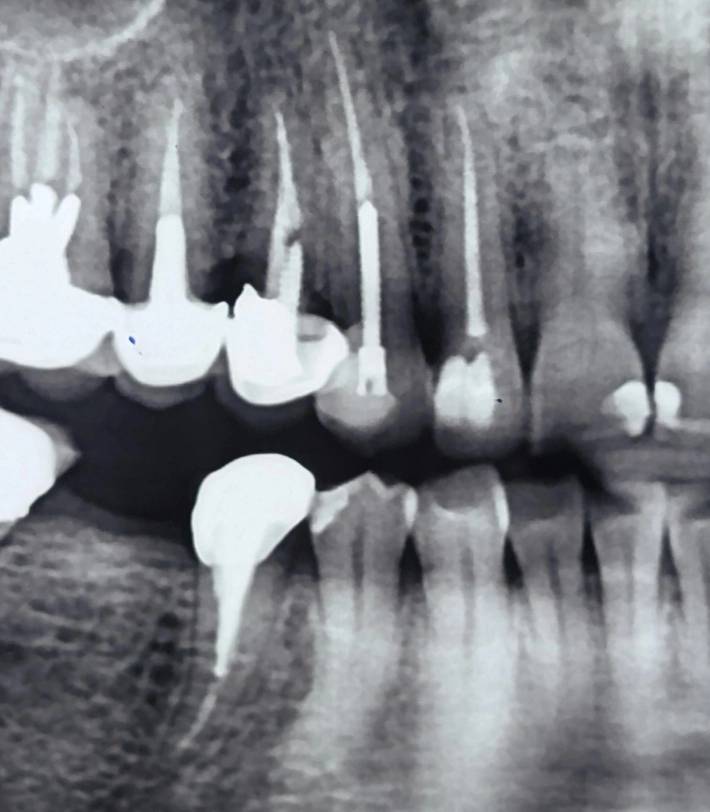

بر اساس رادیوگرافی پانورامیک، به او پیشنهاد کشیدن دندان و جایگزینی با ایمپلنت داده شده بود.

در ارزیابی اولیه، محدودیتهای پانورامیک در تشخیص جزئیات ساختاری مدنظر قرار گرفت

تفاوت میان پانورامیک و پریاپیکال، فقط در وضوح تصویر نیست—

بلکه در سطح تصمیمسازی است.